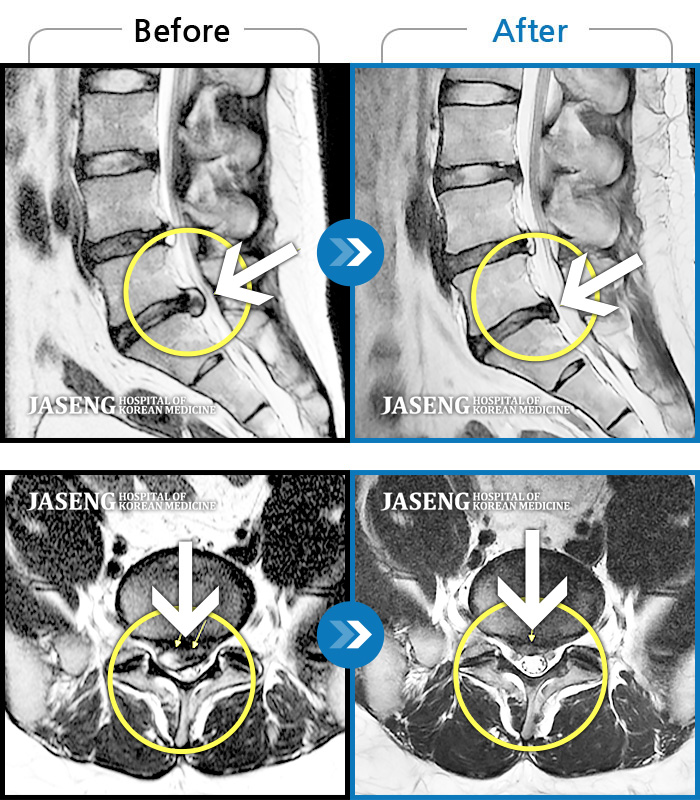

안녕하세요.방금 배아프다고 선생님찾아뵙고 진료받았죠 ㅎㅎ 후기를 이제서야 올리네요. 4년전인가 퇴행성디스크를 진단받고 양방병원 이곳저곳을 전전긍긍하며 속썩었던기억이나네요. 여러병원에서 수술을해야한다는 말에 젊은나이에 걱정을많이했었습나다. 심하게 아플때는 아침에 잠에서깨고 바로일어나지도못하고앉지도못해 회사생활이 힘들었는데 성생님만나뵙고 꾸준한치료 덕에 이렇게 허리가 안아프게되어 너무행복합니다. MRI는다른곳에서 찍어본거긴하지만 돌출된 디스크가 들어갔다는말에 신기했었습니다. 생활습관을바꾸고자 노력했고, 무엇 보다 선생님을 믿고 의지한 결과가아닐까 생각됩니다. 너무 감사드리고 MRI사진은 공유해드려야하는데 자꾸까먹네요 ㅎ